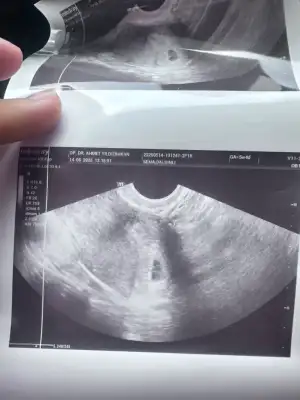

Kızlar keseme bakar mısınız normal mi 5+2 bugün doktor dedi bebek var içinde 10 gün sonra kalp atışına çağirdi

• IMG_3585.webp

IMG_3585.webp

32,4 KB · Görüntüleme: 24